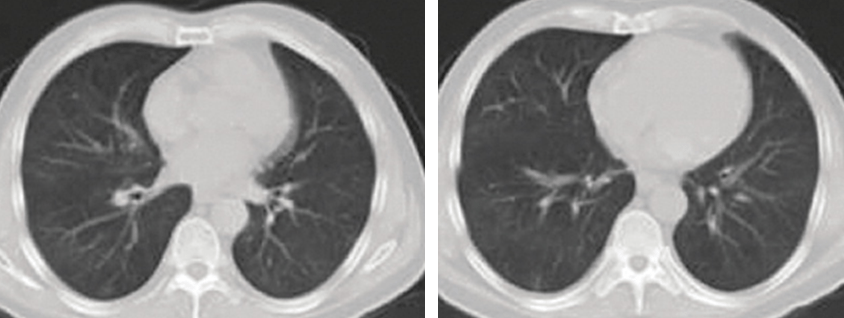

Chest computed tomography (CT) scan showed multiple ground glass appearance in both lungs. She was diagnosed with pneumonia and admitted to hospital. During her stay on a general medical ward, she was prescribed the antibiotic ceftazidime and a patent Chinese herb infusion (Xiyan Ping) for 4 days but showed no significant improvement.

• A third CT scan showed almost complete disappearance of the ground glass appearance. On discharge the patient had complete resolution of symptoms.